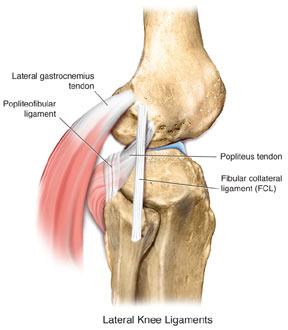

젊고 운동하는 환자분들 중에 생길 수 있는 무릎 외측 인대 손상 입니다. 무릎안쪽에서 바깥쪽으로의 외력이 작용하는 것을 VARUS STRESS 라고 하는데, 이러한 과도한 VARUS STRESS 가 짧은 순간에 가해진 경우 이런 바깥쪽 인대의 손상이 있을 수 있습니다.

외측인대는 앞측 비골 근위부와 원위 대퇴골(lateral epicondyle) 사이에 붙어있습니다.